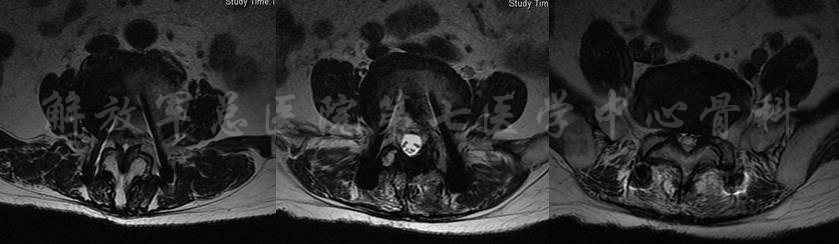

MRI

MRI颈4-5(左)、颈5-6(中)颈6-7(右)

矢状位MRI

轴位MRI:腰3-4(左)、腰4-5(中)、腰5骶1(右)